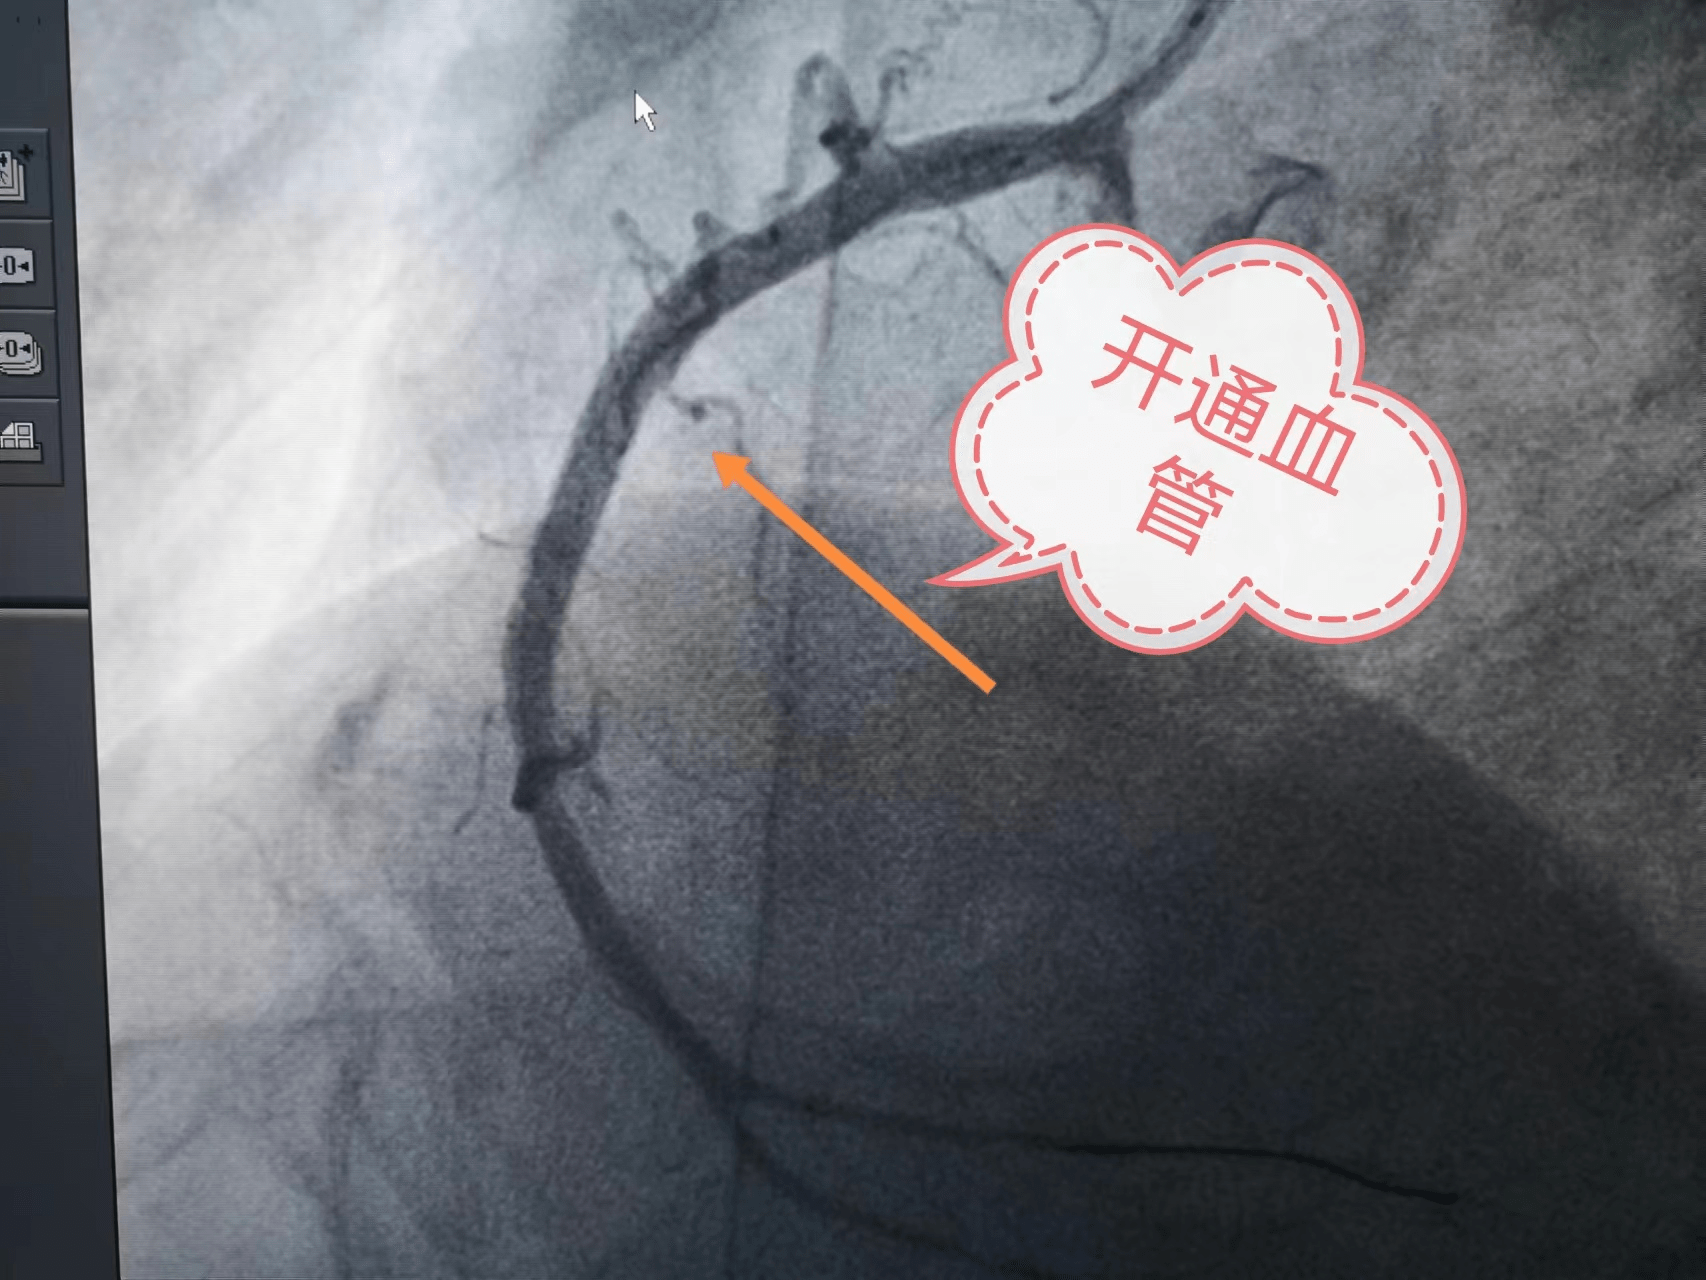

7、无症状性冠心病运动试验阳性伴有明显的危险因素的患者,应行冠状动脉造影以评估冠脉情况CT发现临界狭窄或严重狭窄对于CT检查发现冠脉存在临界狭窄或严重狭窄的患者,需要进行心脏造影以进一步评估血管情况原发性心脏骤停复苏成功应早期进行血管病变干预治疗,需要评价冠状动脉情况总之,心脏造影是一项。

18、心脏造影属于比较小的手术,因此危险性也比较小造影通常在穿刺之前需要局部注射麻药,之后使用比较粗的针从桡动脉位置做穿刺,再送入一根导管进入主动脉根部,即主动脉窦处,通过主动脉窦进入心脏的血管中,包括左主干前降支左旋支右冠状动脉给动脉注射入造影剂之后进行照相,照相完成后,整体的。